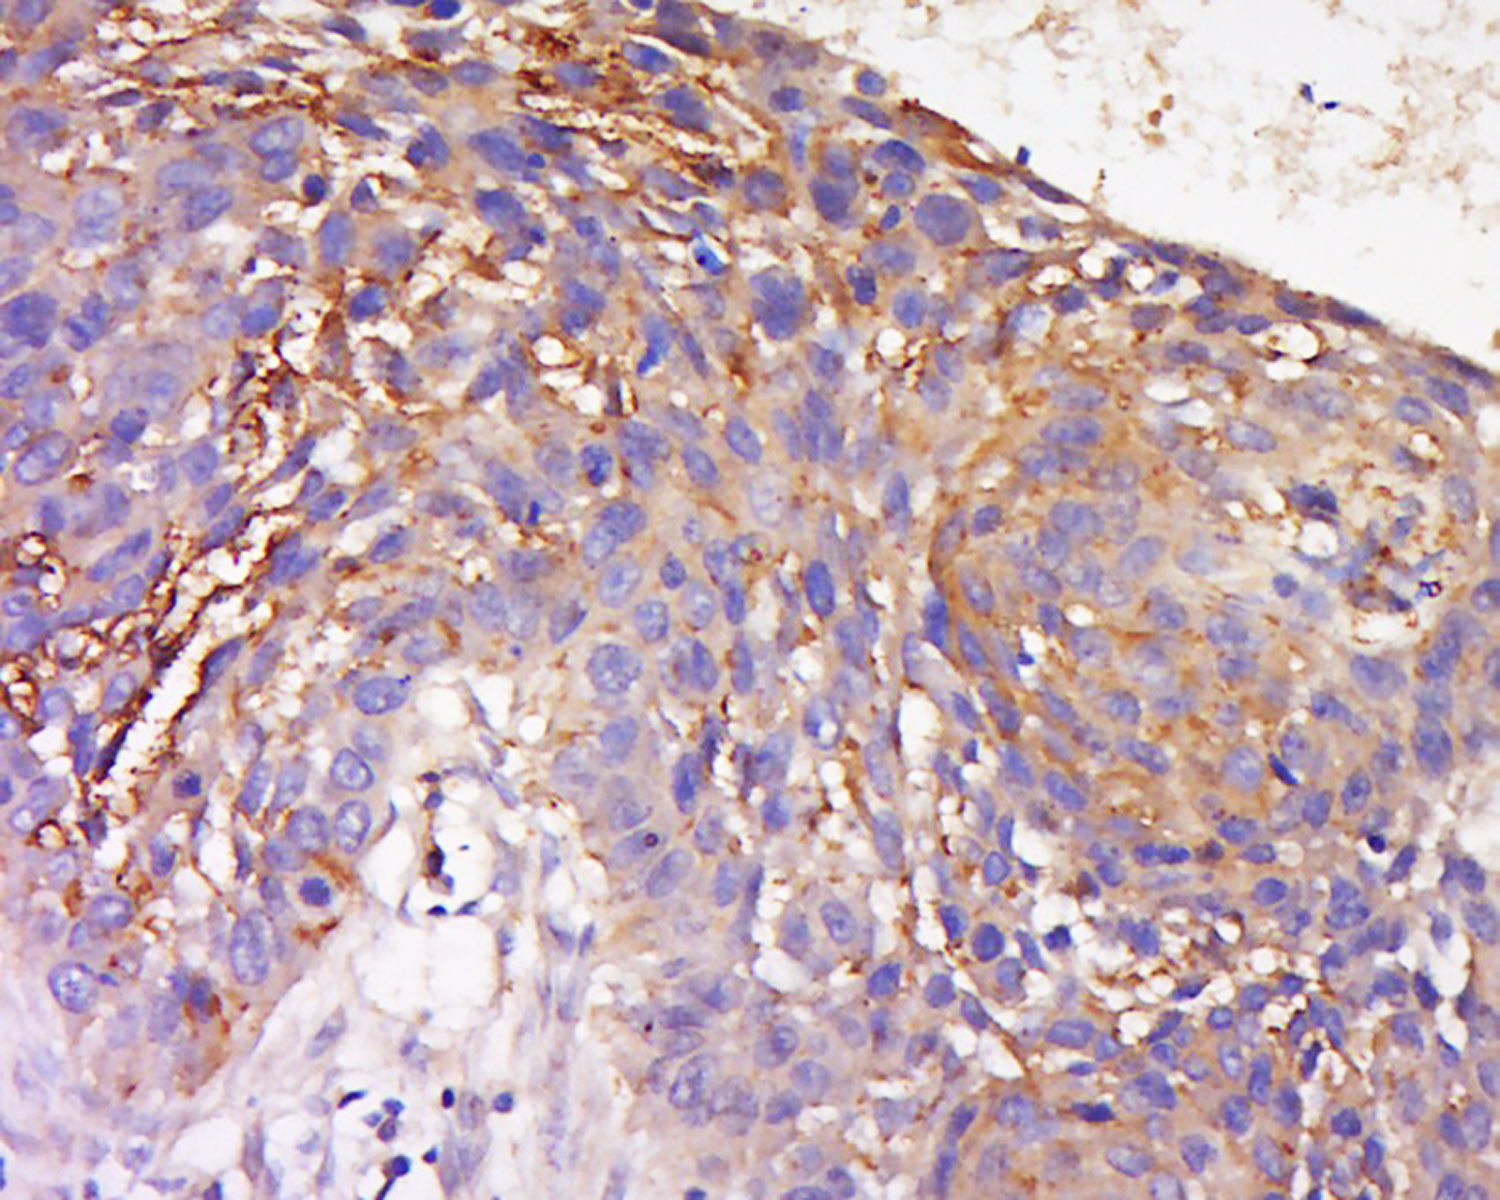

Tissue/cell: Human lung carcinoma; 4% Paraformaldehyde-fixed and paraffin-embedded; Antigen retrieval: citrate buffer ( 0.01M, pH 6.0 ), Boiling bathing for 15min; Block endogenous peroxidase by 3% Hydrogen peroxide for 30min; Blocking buffer (normal goat serum,C-0005) at 37℃ for 20 min; Incubation: Anti-TRAM1 Polyclonal Antibody, Unconjugated(bs-16565R) 1:200, overnight at 4°C, followed by conjugation to the secondary antibody(SP-0023) and DAB(C-0010) staining